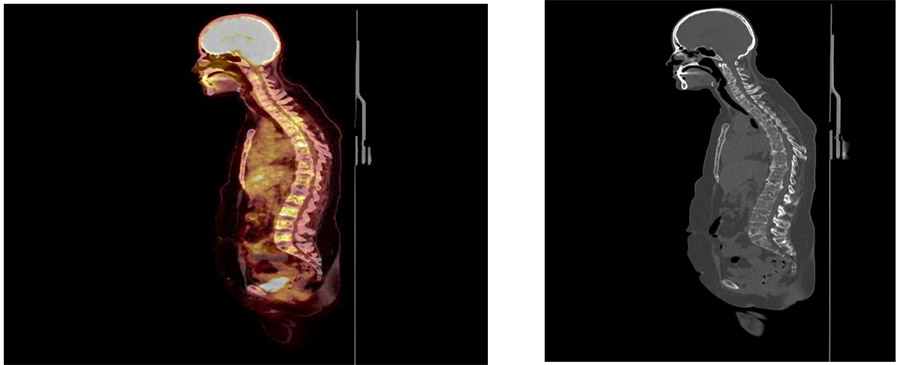

Before the surgery: PET-CT shows multiple metastases and compression fractures.